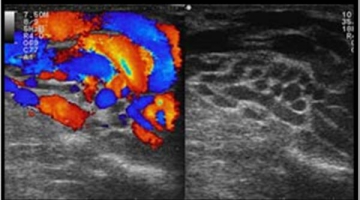

.Ειδικός Ιατρός Ακτινοδιαγώστης στη Euromedica Καρδίτσας, με ιδιαιτερότητα στους υπερήχους μαστών και θυρεοειδούς αδένα